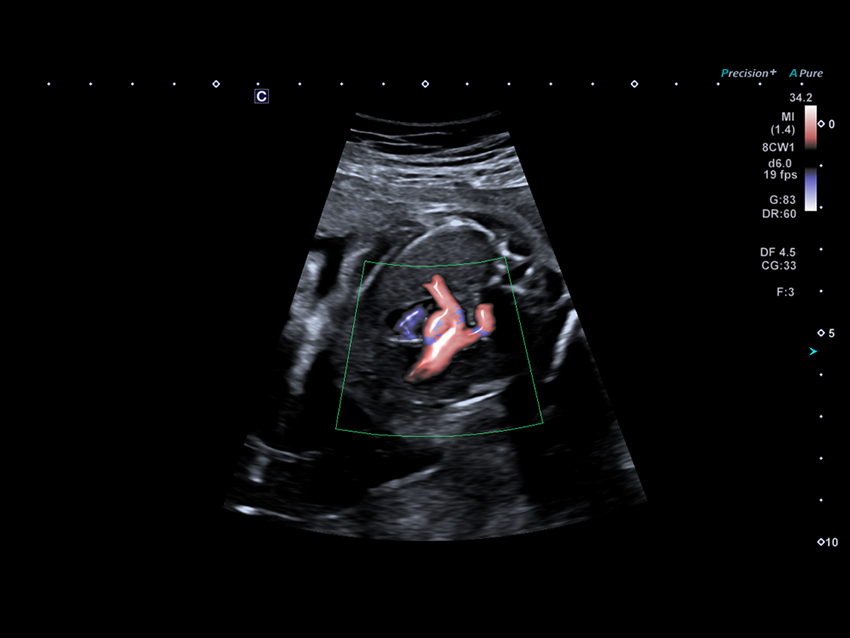

Технологія Advanced Dynamic Flow (ADF) підтримує просторову та часову роздільну здатність за допомогою короткоімпульсної доплерівської візуалізації, що забезпечує гемодинамічну оцінку серця плода з високою роздільною здатністю.